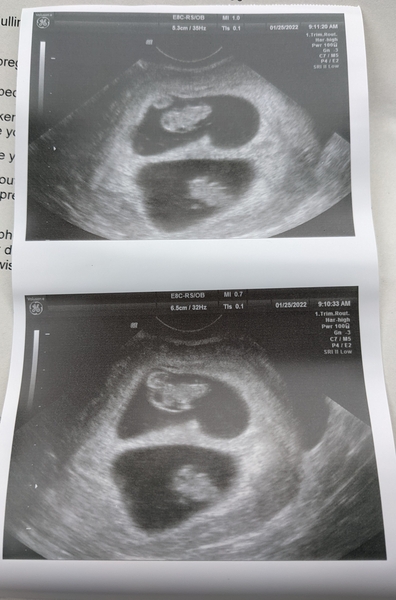

Hi everyone! So my due date is 8th September, however we're having twins!!

So will almost definitely be August birth :) I am 7 weeks 5 days, and had an early scan today :)

(Was through IVF hence knowing the exact dates!)

Omg TWINS! Congratulations 🥳 did you have a feeling or was it a complete surprise?

@miltonj @SantiagoSister well we had a blood test to check for pregnancy as it was through IVF, and my hcg level at 4 weeks was 6000+, which... is very high, which hinted towards twins. Apart from that, I don't think I've been that bad with symptoms! I get nausea mostly at bedtime, but haven't been sick. And have felt the odd cramping/pinching in my abdomen and been bloaty and not wanting to eat lots at once. Apart from that and the odd tiredness, that's it so far!

Yeah there's defo a lot to think about, bet it's a bit overwhelming, but you'll just slip into a routine! Do you know what kind of twins? Separated egg or two eggs fertilised? Sorry if that a stupid question, I don't know that much about twins!

Caslo · 25/01/2022 20:18

@miltonj Just gonna jump in and suggest they're fraternal/non identical twins since there are two sacs. I'm not an expert (hopefully someone who is an expert will be along shortly to confirm) but I think with identical twins there is only one sac and both babies share it. Huge congratulations @starkid you're so lucky! I was so hoping for twins but only the one here for me Smile you'll manage absolutely brilliantly I'm sure, plenty of time to get your head around it and to plan x